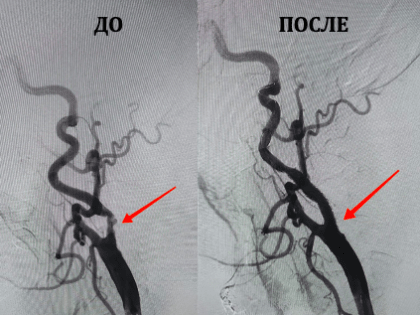

Ангиогирурги «Пироговки» впервые выполнили стентирование сонных артерий

Символично, что первая операция состоялась в преддверии Международного дня борьбы с инсультом, который отмечается 29 октября.

Впервые выполнили стентирование сонных артерий врачи мурманской «Пироговки»

Мурманский многопрофильный центр имени Пирогова впервые получил федеральные квоты на такие виды операций.